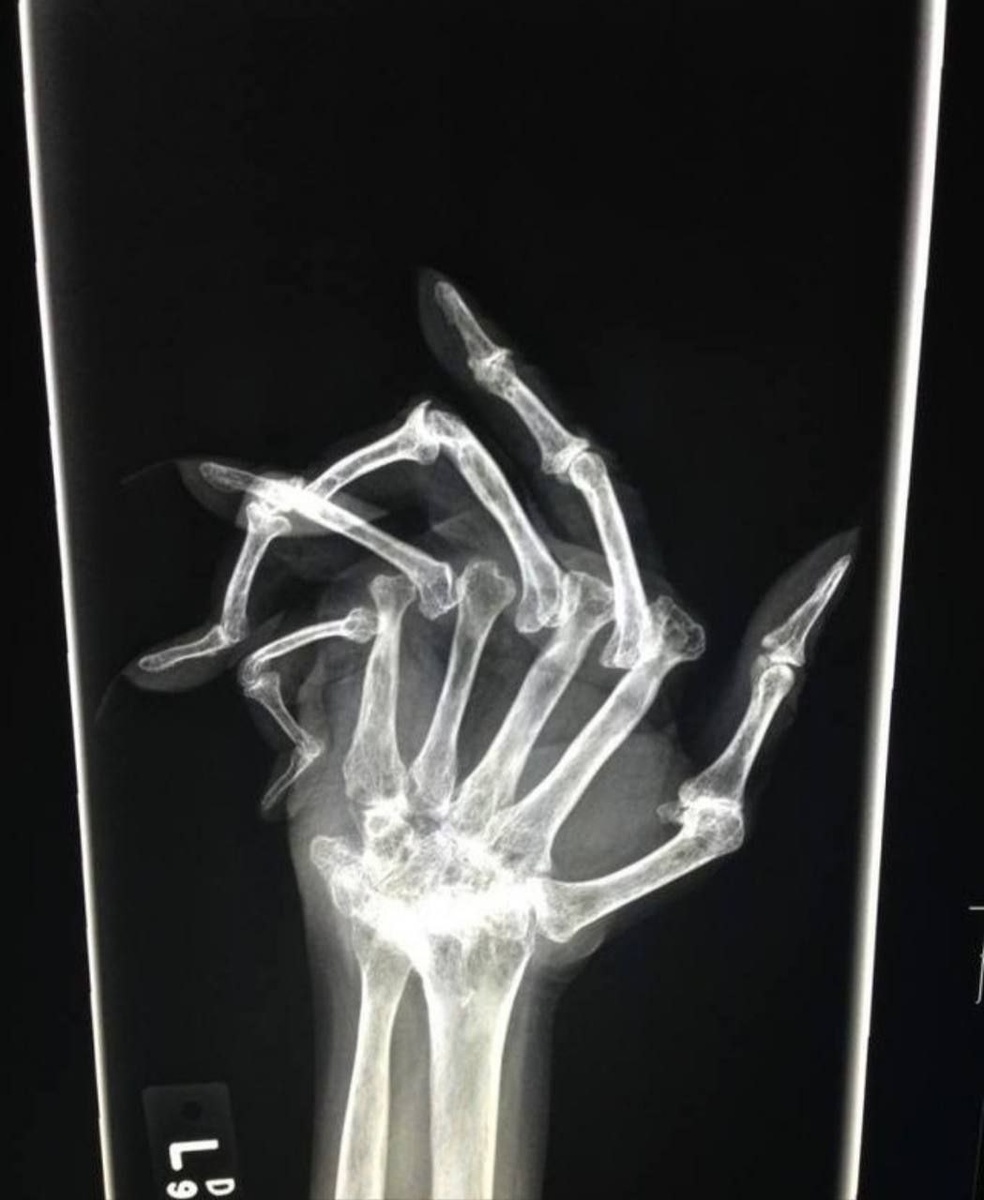

На рентгене - последствия запущенного ревматоидного артрита

На рентгене - последствия запущенного ревматоидного артрита❗